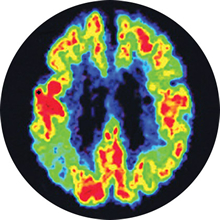

Using brain scanning techniques, such as positron emission tomography (PET), researchers have discovered something else in the brains of people with Alzheimer’s:

Alzheimer’s disease brain

Diminished cerebral

glucose metabolism

Image source: Small GW, Ercoli LM, Silverman DHS, et al. Cerebral metabolic and cognitive decline in persons at genetic risk for Alzheimer's disease. Proc Natl Acad Sci USA. 2000;97(11):6037-6042. Copyright 2013 National Academy of Sciences, U.S.A.

- Diminished cerebral glucose metabolism – or glucose hypometabolism, means that neurons have difficulty producing the energy they need to function. Neurons normally use glucose (a type of sugar) as the primary fuel source to power the brain’s daily activities. In Alzheimer’s disease, scientists have discovered that the engines inside neurons malfunction, so that even if there is enough glucose in the body, the brain cannot use it properly. This most often occurs in the areas of the brain involved in memory and cognition, and it can begin years, sometimes decades, before any symptoms of the disease appear